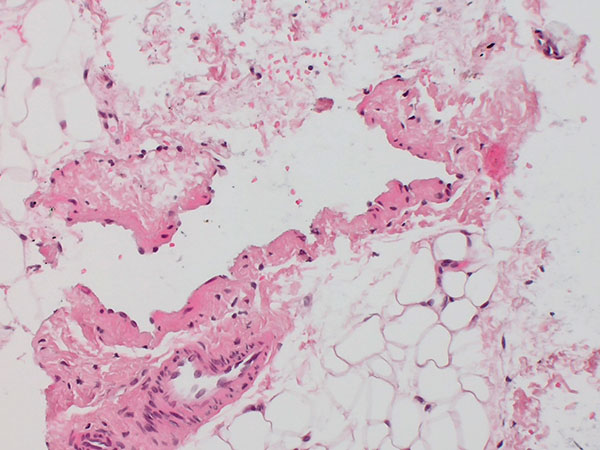

Histopathological image, hematoxylin & eosin stain (HE), here 25-fold overview magnification: A dysplastic, vein-like irregular vascular cavity is found. This is embedded in normal adipose tissue and stroma.

Histopathological image, hematoxylin & eosin stain (HE), here in 200x magnification: An "empty space" lined with endothelium with single, centrally contained erythrocytes and a malformed, thin venous vessel wall is visible. The "empty space" is bordered on the outside by vascular endothelial cells. A normal arteriole is visible next to it.